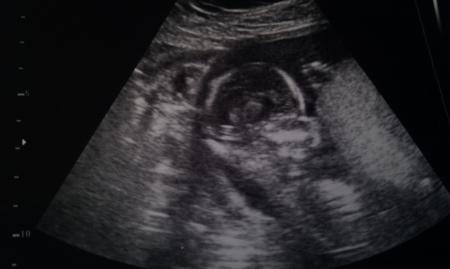

...und toll wars....:) erst Us von außen... würmle hat aber schön die Beinchen zusammengedrückt.... Machte dann Us von innen...und siehe da... wird wohl kein Mädchen werden....:) Sind stolz wie Oskar und die Große Schwester erst, Sie wollte unbedingt nen Bruder:) Aba ich wart auf jedenfall den nächste Termin noch ab bevor wa andere erfahren was es wird..:) Bubi is schon ganze 17 cm groß und wiegt 160 g laut us. Hihi hänge ma meine Bilder an... LG

Bild zu wieder da vom Termin - Forum für April - Mamis

Und nach dem halloween Bildchen noch eins von der Seite....